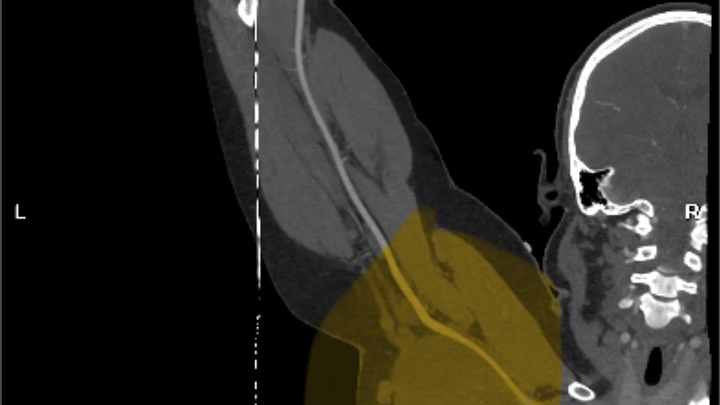

My last surgery was early last year, and recovery has gone well, but a relatively new problem has come up. In the last year or two, we discovered that a tumor in my left arm has been growing pretty aggressively and is starting to concern doctors enough that they are planning surgery. Hopefully, by the end of January or early February, this time surgery is slightly more risky than my previous ones due to the number of nerves that are running through the tumor. They are predicting about a 10% chance of losing feeling in parts of my arm and a slight chance I lose the ability to use my arm at all.